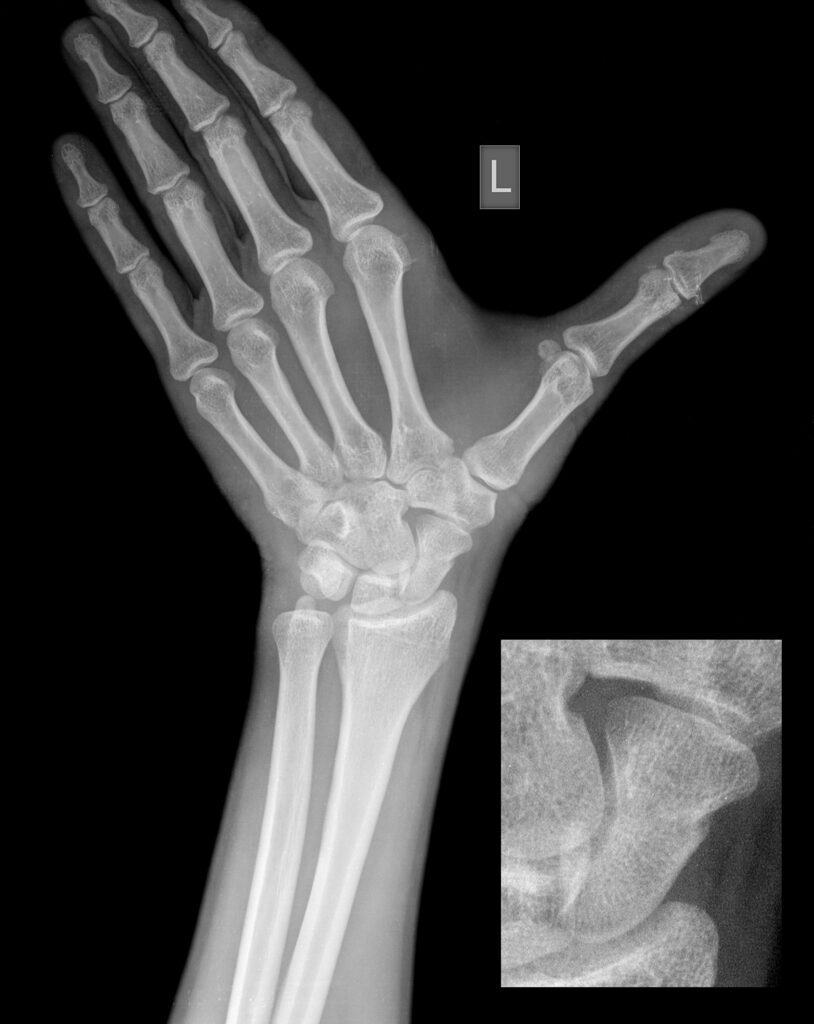

IMAGING

Suggest X-ray, suggest CT

DIAGNOSING SCAPHOID FRACTURE

A fractured scaphoid is a common wrist injury, many may think of it as a fractured wrist, or simply a sprained wrist. The cause is a fall on an outstretched hand where undue load is distributed through the wrist causing the small scaphoid bone to fracture or break.

Most people experience pain or swelling around the base of the thumb and into the wrist (the anatomical snuff box) with a fractured scaphoid. In many cases it’s likely there will be no visible deformity and many dismiss the problem as a sprain and fail to seek proper medical attention and advice leading to the development of other issues.

Our Hand Therapists, Physiotherapists and Occupational Therapists are experienced in reading X-rays and CT’s for Scaphoid Fracture and they will be able to guide your treatment depending on the severity of your Scaphoid Fracture.

Action Rehab Hand Therapy Clinic hand therapists can assess, advise, and treat broken scaphoids and seek specialist surgical opinion when required. Our therapists have the ability to read X-rays and CT scans and the Hand Therapist at Action Rehab Hand Therapy Clinic can assess medical imagery deciding the most appropriate treatment plan for your Scaphoid Fracture.

Choosing the right Hand Therapist starts with them being able to read your X-rays and then fabricate the right brace for you. The therapists at Action Rehab Hand Therapy Clinic are experienced in assessing and reading X-rays and assessing your Scaphoid Fracture.